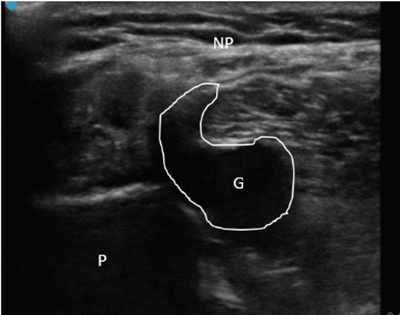

Ante estos hallazgos se decidió realizar ecografía clínica, objetivándose datos de neuropatía del nervio peroneo común (nervio engrosado, hipoecogénico y con pérdida del patrón fibrilar previo a su entrada en el túnel osteofibroso peroneo) coincidiendo con la compresión de una estructura compatible con un ganglión originado en la articulación tibio-peronea proximal. En ecografía dinámica, ante maniobras de flexo-extensión de pie, se objetivó un ascenso del ganglión y un mayor contacto con el nervio peroneo (Figura 1) a nivel de la zona de afectación neural. El paciente presentaba además un claro tinel ecográfico positivo a la compresión nerviosa y dolor a la ecopalpación del ganglión.

Fig. 1. Ecografía de corte axial del nervio peroneo común con características de neuropatía por compresión de ganglión. P: peroné. G: ganglión, resaltado perímetro para mejor visualización. NP: nervio peroneo común, que se encuentra engrosado, hipoecogénico y con pérdida del patrón fibrilar.